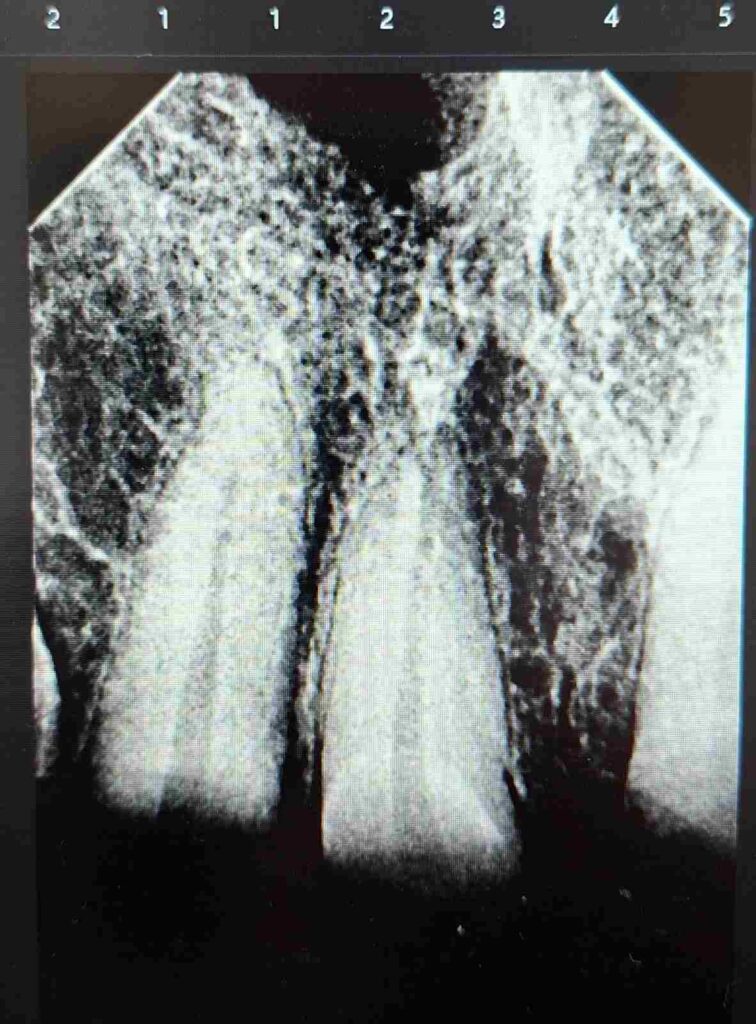

Tras la evaluación clínica y radiográfica detallada, se indicó tratamiento endodóntico en los dientes 11, 12, 21 y 22 con el objetivo de restablecer la salud del sistema de conductos radiculares y crear una base biológica sólida para la posterior rehabilitación protésica del sector anterior.

Durante todo el protocolo se realizaron irrigaciones activas con soluciones desinfectantes, garantizando la eliminación completa de detritos y microorganismos. Finalmente, se completó la obturación tridimensional del sistema radicular, logrando un sellado hermético confirmado por control radiográfico.